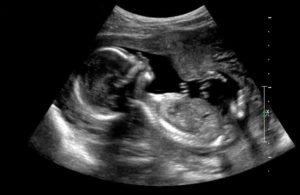

Для точной диагностики проводится абдоминальное или влагалищное ультразвуковое исследование.

Сердце плода узи срок. Узи при беременности.

Ребенок на 18 неделе активно растет и развивается. Будущая мама начинает чувствовать нежные движения ребенка. Беременные с нетерпением ждут этого, так как первое шевеление является одним из самых волшебных событий в течение всей беременности.

Органы ребенка начинают функционировать с восемнадцатой недели беременности. В связи с этим женщина может испытывать некоторые спазмы и заметить белые, выделения из влагалища. Ребенок сейчас примерно 200 грамм и его рост около 1 сантиметров в длину. Его легочная и сосудистая системы стремительно развиваются.

Ребенок может глотать околоплодные воды и производить меконий. Меконий — первое испражнение, которое он сделает. Это хорошая новость, так как это значит, что его пищеварительная система начинает работать. На этой неделе развиваются отпечатки пальцев, создавая уникальный рисунок руки ребенка. Теперь еще больше кровеносных сосудов можно увидеть через его прозрачную кожу.

Боли на 18 неделе беременности вполне нормальное явление. Растяжения коже, и рост живота могут вызвать боль и судороги в нижней части живота. Это пугает многих молодых мам, но это совершенно нормально. Боли на 18 неделе связаны с напряжением матки, и так как матка становится, все больше связки находятся в напряжении.

Боли в 18 недель беременности могут быть острыми и могут ощущаться по обе стороны от живота. Как правило, спазмы быстро утихают. Тем не менее, если на 18 неделе болит живот, то следует обратиться к врачу. Нужно обратить внимание как спазмы приходят и уходят, и насколько они регулярны, и какой между ними интервал.